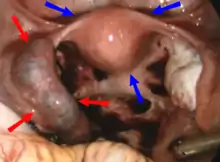

| Laparoscopic view, looking down at the uterus (marked by blue arrows). In the left fallopian tube, there is an ectopic pregnancy and bleeding (marked by red arrows). The right tube is normal. | |